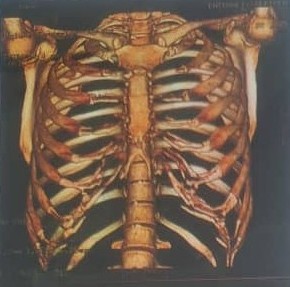

از کجا بفهمیم دنده، هنوز غضروف داره؟

گاهی پیش می آید در بعضی از افراد با اینکه در سنین جوانی هستند، غضروف های دنده به استخوان تبدیل شده اند و طبیعتا غیر قابل استفاده برای ترمیم بینی میشوند. گاهی هم افراد مسن تصمیم به جراحی ترمیمی بینی میگیرند، و این مهم هست که ما بدانیم، آیا غضروف های دنده همچنان سالم و قابل استفاده هستند یا خیر.

برای تشخیص اینکه دنده هنوز غضروف کافی دارد یا خیر، سادهترین و دقیقترین روش سیتیاسکن از جدار قفسه سینه است. در این تصویربرداری مشخص میشود که غضروفها سالم هستند یا به مرور زمان استخوانی شدهاند.

- سیتی اسکن از بینی و جدار قفسه سینه برای ارزیابی محل برداشت غضروف